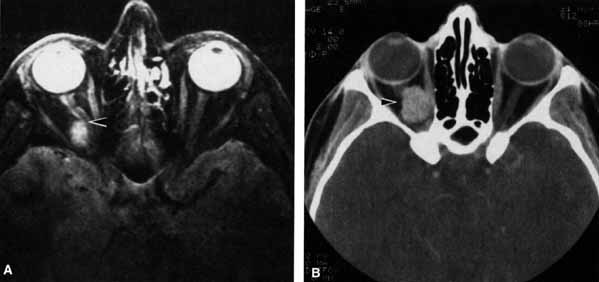

Fig. 6 T2-weighted magnetic resonance imaging (MRI) shows cerebrospinal fluid (CSF) surrounding the optic nerve within the subarachnoid space (arrow). The CSF extends to the posterior pole of the globe. An optic nerve meningioma is present on the contralateral side.

The optic nerve remains vulnerable to compression within the bony confines of the orbit. Compressive optic neuropathy is most likely to occur where the optic nerve is tethered to the bone, that is, at the orbital apex (Fig. 7A). The optic nerve in other areas of the orbit can be displaced markedly without suffering vision loss (Fig. 7B).

Fig. 7 A. A cavernous hemangioma measuring 1.5 cm in longest dimension is located at the orbital apex displacing the optic nerve (arrow). Visual acuity is 20/40. there is a relative afferent pupil defect, and visual field shows a central scotoma. B. A cavernous hemangioma measuring 2 cm in longest dimension is located in the midorbit displacing the optic nerve (arrow). Visual acuity is 20/20. There is no relative afferent pupil defect and the visual field is normal.